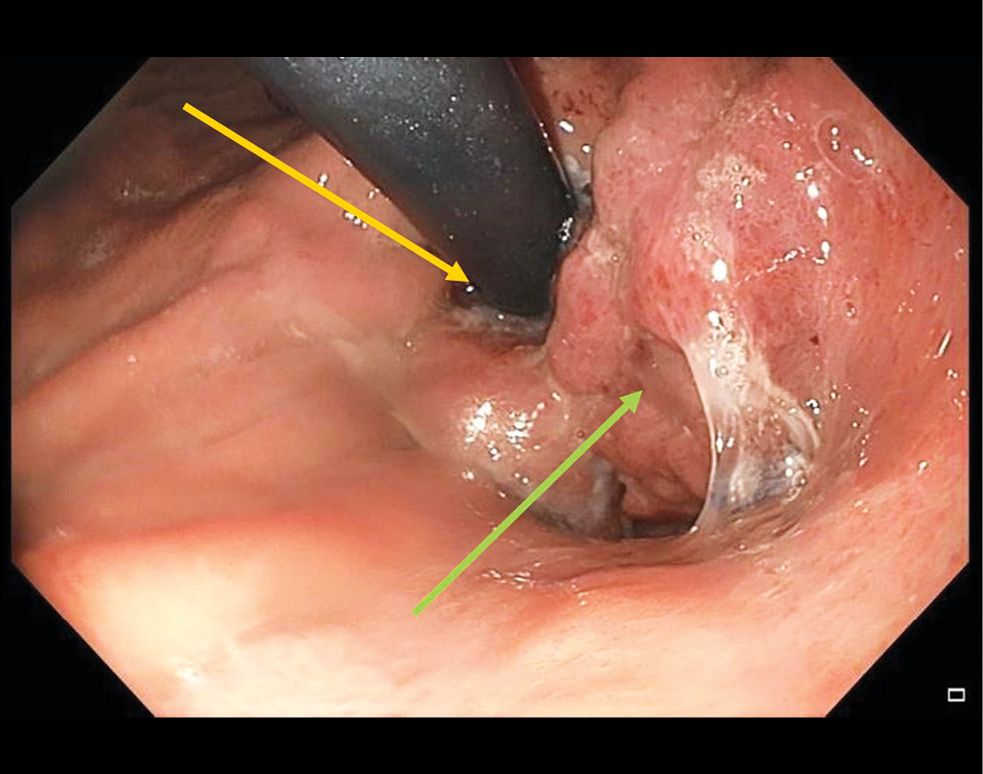

The patient was referred to a tertiary cancer center. Endoscopy at the cancer center showed the proximal edge of esophageal tumor infiltration at a site 24 cm from the incisors. The tumor appeared as multiple whitish-red merging lesions that spread circumferentially to the subcardial stomach. Deep ulcers covered with fibrin and necrotic plaque were observed. A fistula opening was found in the tumor tissue at a site 36 cm from the incisors, with the creamy opalescent contents flowing into the lumen. The esophageal lumen was significantly narrowed by the exophytic component of the tumor (Fig. 3). The tumor tissue was dough-like in texture and bled easily upon contact. The circumferentially infiltrated cardioesophageal junction was visualized at a site 44 cm from the incisors. The tumor infiltrated along the posterior wall to the subcardia (Fig. 4).

Fig. 4. Endophoto. Barrett`s stenosing adenocarcinoma. The yellow arrow marks the endoscope located at the entrance to the stomach, the green arrow marks the tumor tissue.